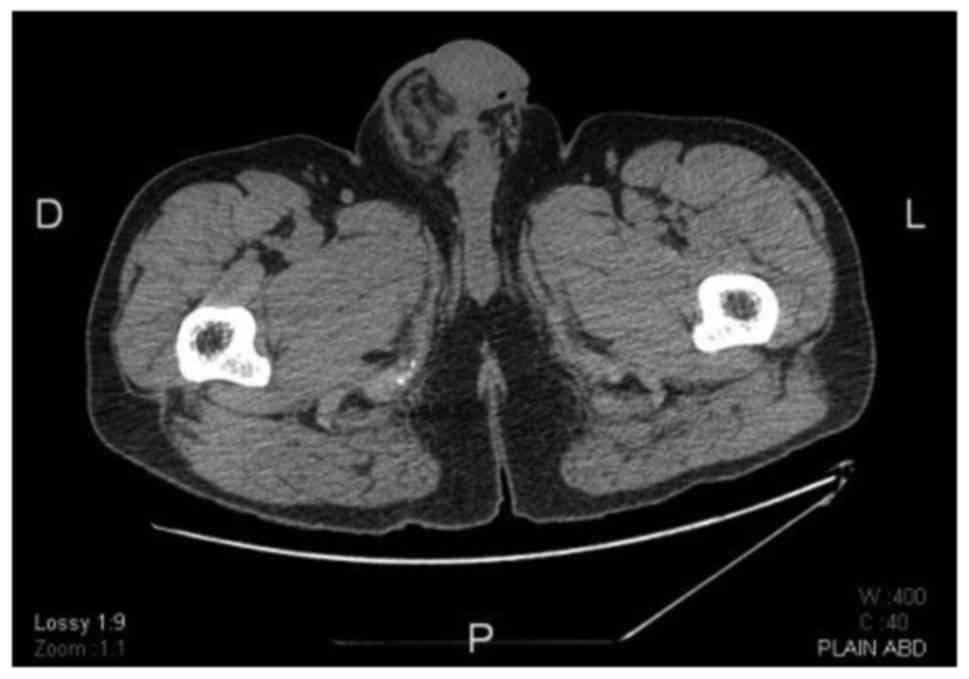

A computed tomography (CT) scan revealed a 5-cm mass with heterogeneous enhancement located inside the right inguinal canal, surrounded by local inflammation. Despite the atrophic appearance of the ipsilateral testis intraoperatively, on CT scan it appeared to be enlarged due to the thickening of the overlying layers (Fig. 2).

Figure 2.

Computed tomography scan at the level of the scrotum demonstrating thickening of the layers overlying the right testis, as well as the surrounding inflammatory reaction.